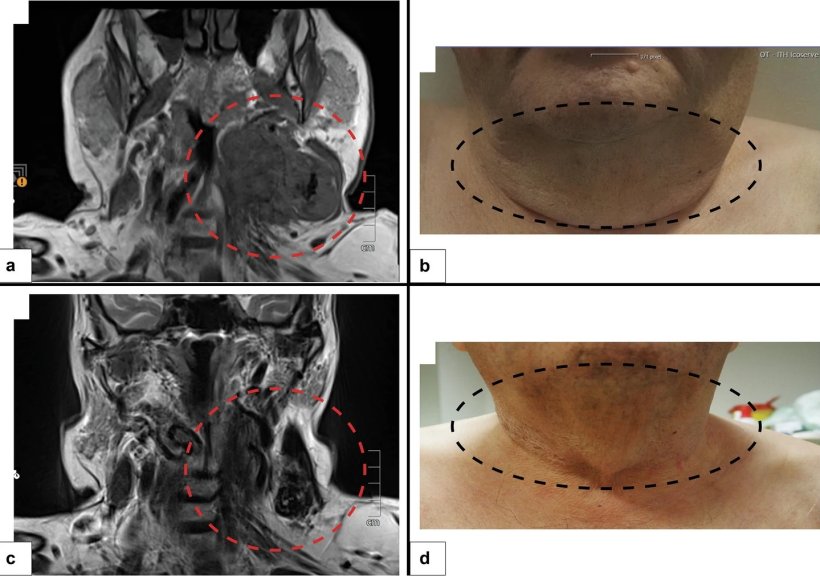

Im Fokus stand ein extraskelettales Osteosarkom – ein äußerst seltener, aggressiver Weichteiltumor, der sich außerhalb der Knochen entwickelt und schnell ausbreitet. Bislang standen für diese Art von Tumoren nur sehr begrenzte Behandlungsmöglichkeiten zur Verfügung. Am Diagnostik- & Forschungsinstitut für Pathologie der Med Uni Graz gelang es weltweit erstmals, bei dieser Tumorentität eine spezifische genetische Veränderung nachzuweisen.

Diese präzise molekulare Diagnose wirkte sich unmittelbar auf die Patientenbetreuung aus: Die betroffene Person konnte gezielt mittels TRK-Inhibitor behandelt werden. Die Therapie zeigte rasch Wirkung, führte zu einer deutlichen Tumorverkleinerung und zu einem anhaltenden Behandlungserfolg – bei guter Verträglichkeit und initialer Inoperabilität des Tumors.